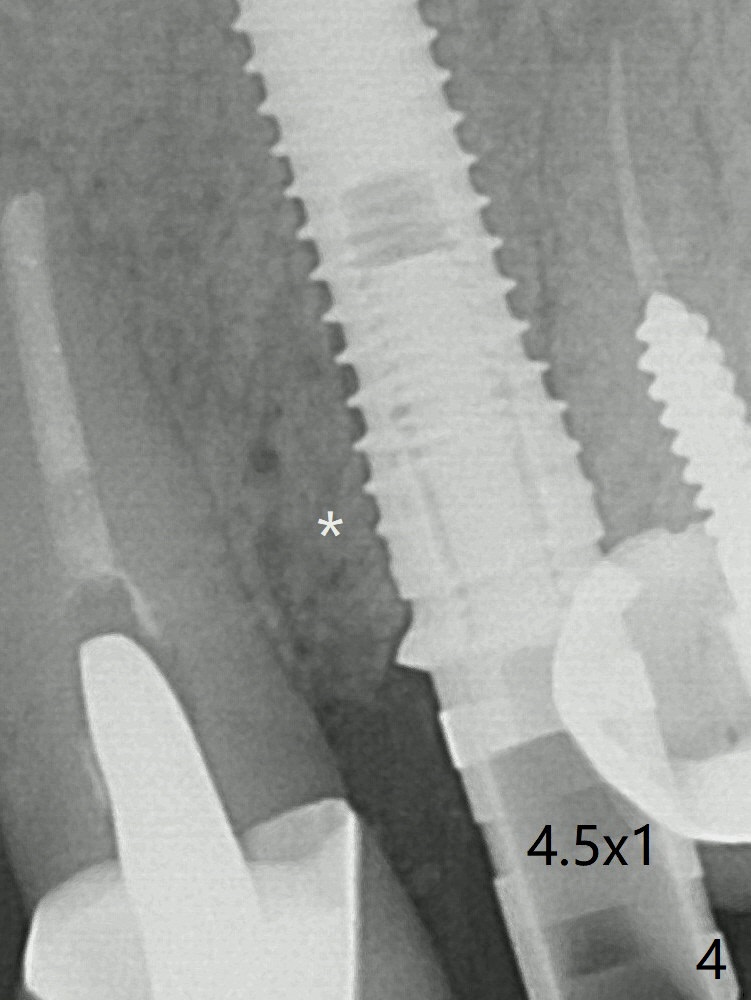

In spite of severe apical infection (Fig1,2 *), a thin narrow strip of the buccal plate (arrowheads, corresponding to the keratinized gingiva) is present when the tooth #11 is extracted.  The thin bone keeps the bulging alveolus, i.e., reservoir for bone graft (Vanilla/Osteogen Fig.4 *) after placement of a 3.8x16 mm implant (Fig.3,4).  A 4.5x1 mm temporary abutment, placed and trimmed for an immediate provisional, seems to be short in cuff.  When an implant is placed deep to prevent periimplantitis, the cuff should be longer, i.e., 3 mm.  X-ray should be taken for the depth confirmation after temporary abutment placement.  Fig.3: a 2 mm drill in place, 18 mm in bone vs. 16 mm of implant placed ~ 2 mm subcrestal (Fig.4).  A narrow implant (3.8 mm) is chosen over 4.5 mm because of the extensive buccal plate defect.  While the hard tissue around the implant seems to be healthy 5 months postop (Fig.7), the soft tissue is not (Fig.8).